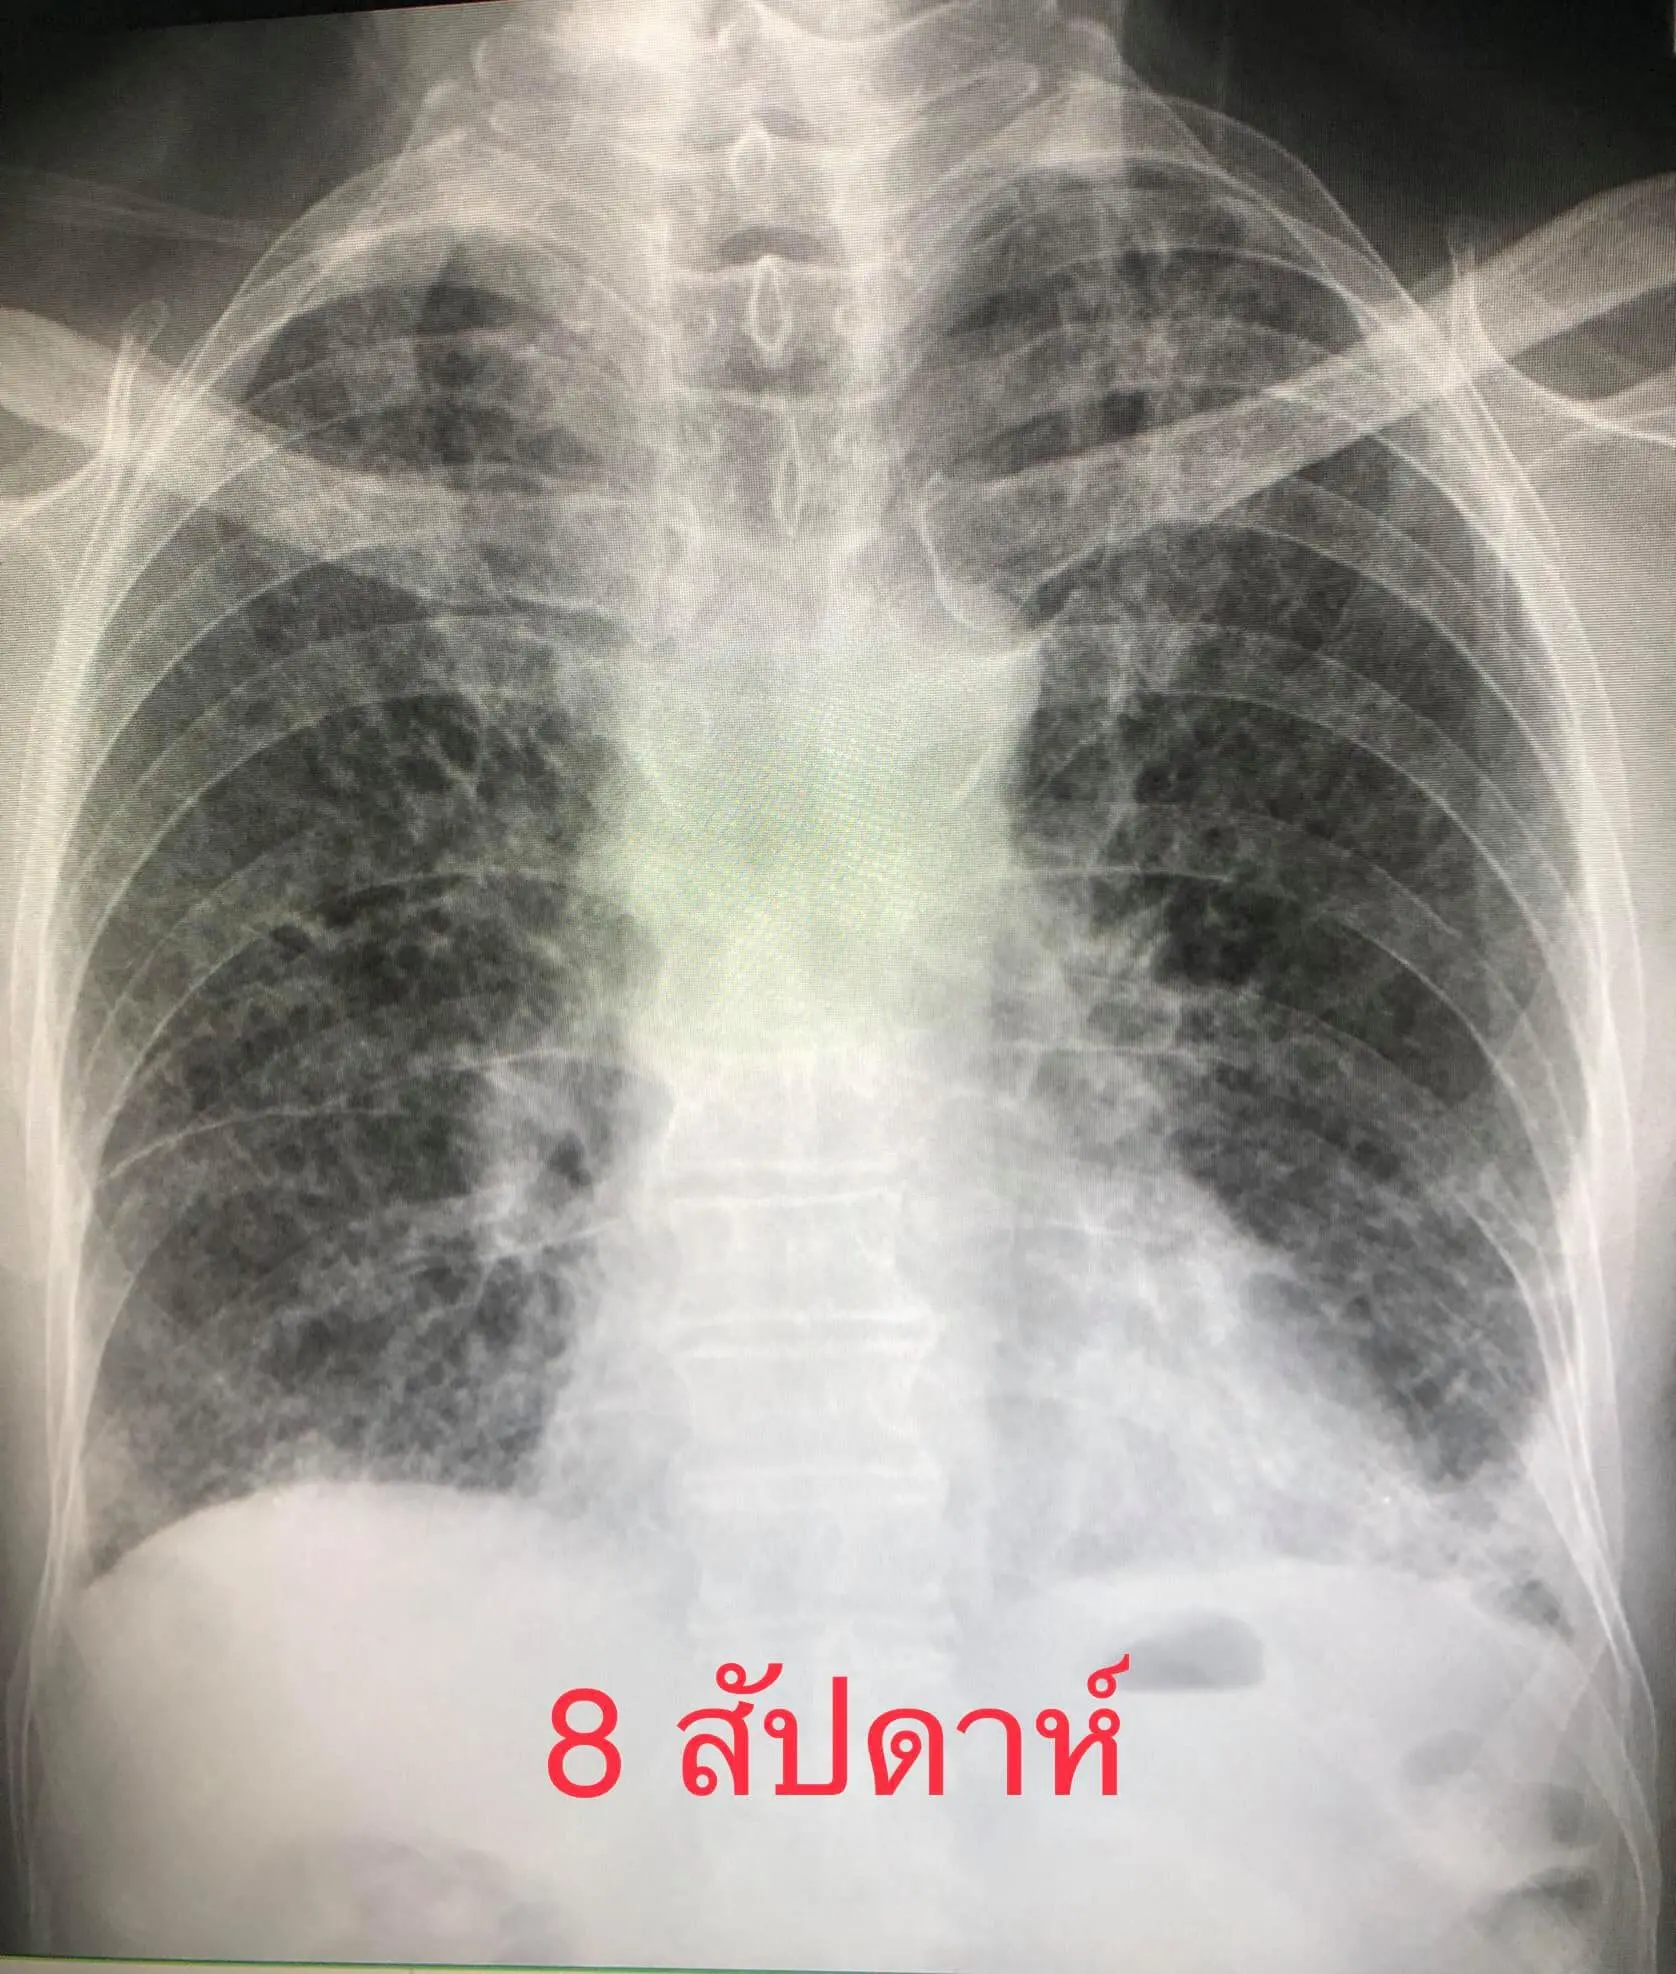

8 สัปดาห์หลังจากเริ่มป่วย มีไอเล็กน้อย ไม่มีไข้ เดินนิดเดียวก็เหนื่อย ยังต้องใช้ออกซิเจน 4 ลิตร/นาทีตลอดเวลา ระดับออกซิเจนในเลือดถึงจะขึ้นมาอยู่ที่ 95% แต่ถ้าไม่ใช้ออกซิเจน ระดับออกซิเจนในเลือดจะลดลงต่ำกว่า 80% เอกซเรย์ปอดยังผิดปกติ ลักษณะคล้ายพังผืด แต่ดีขึ้นช้าๆ (ดูรูป)ไวรัสโควิด-19 มีผลกระทบระยะยาวต่อปอด (Post-Acute Sequelae of SARS-CoV-2 infection)